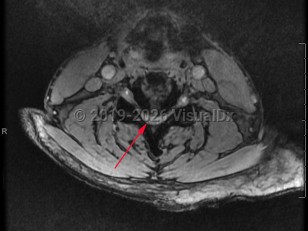

Cervical spinal stenosis

Cervical spinal stenosis is the narrowing of the spinal canal in the neck. Asymptomatic spinal stenosis may be discovered incidentally on imaging, but when it causes impingement of the spinal cord or nerve roots, symptoms can include weakness of the extremities, numbness / paresthesias, and neuropathic / radicular pain.

Narrowing of the cervical spinal canal can result in myelopathy that will result in upper motor neuron signs, such as hyperreflexia, especially in the lower extremities. Patient may experience walking difficulties or ataxia. Neck pain is common. Narrowing of the neural foramina in the cervical spine will often cause a radiculopathy. Compression of the cervical nerve roots can result in lower motor neuron signs in the upper extremities, which may result in muscle atrophy and fasciculations. Symptoms typically worsen with extension of the spine and improve with flexion.

Spinal stenosis can be congenital, but more typically it is acquired. It most frequently presents in the sixth decade of life or later due to degenerative changes to the spine that result in progressive narrowing of the spinal canal and/or neural foramina. It is also possible that people with congenitally narrow spinal canals are more likely to experience symptoms during the process of aging. Other risk factors for the development of spinal stenosis include inflammatory arthropathies such as rheumatoid arthritis, traumatic injuries, and neoplastic disease.